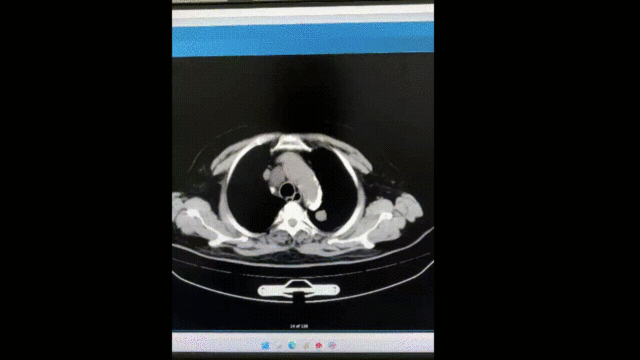

现病史:患者于 2024 年 5 月 18 日行腹部 CT 平扫显示,右肾上级占位,密度欠均匀,大小约 5.5X7.3cm,行强化 CT 示右肾占位,考虑透明细胞 ca 可能性大,双肺多发结节,不除外转移。患者无腰背部胀痛,无血尿,无尿频,尿急,尿痛等症状,无排尿困难,无发热等症状,未行特殊治疗,患者为求进一步诊治,来我院门诊就诊,门诊以「右肾肿瘤」 收入院。

全身评价:胸部 CT 示双肺多发转移,转移不除外;ECT 肾功能显像示右肾功能中度受损

双肺多发结节及肿块,纵隔肿大淋巴结,考虑转移支气管炎

心脏增大,心包积液,冠状动脉钙化左肾囊肿可能,请结合超声左肾周桥隔增厚